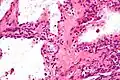

| Micrograph showing a pancreatic serous cystadenoma. H&E stain. | |

Pathologists classify serous cystic neoplasms into two broad groups. Those that are benign, that have not spread to other organs, are designated "serous cystadenoma".[5] Serous cystadenomas can be further sub-typed into microcystic, oligocystic (or macrocystic), solid, mixed serous-endocrine neoplasm, and VHL-associated serous cystic neoplasm. This latter classification scheme is useful because it highlights the range of appearances and the clinical associations of these neoplasms. Serous cystic neoplasms that have spread ("metastasized") to another organ are considered malignant and are designated "serous cystadenocarcinoma".